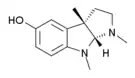

Opium alkaloids and derivatives

Phenanthrenes naturally occurring in (opium):

Semi-synthetic alkaloid derivatives